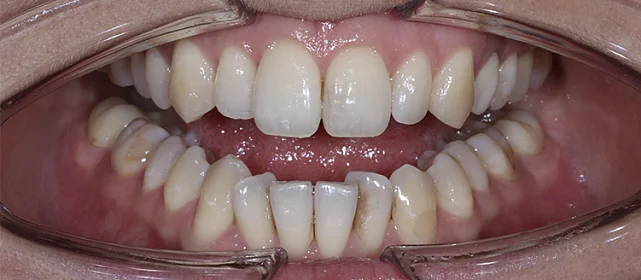

Установка ретейнеров на нижнюю и верхнюю челюсть

Фотографии опубликованы с согласия пациента

Дьячкова Инна Владимировна

Стоматолог - ортодонт

Стаж более 11 лет